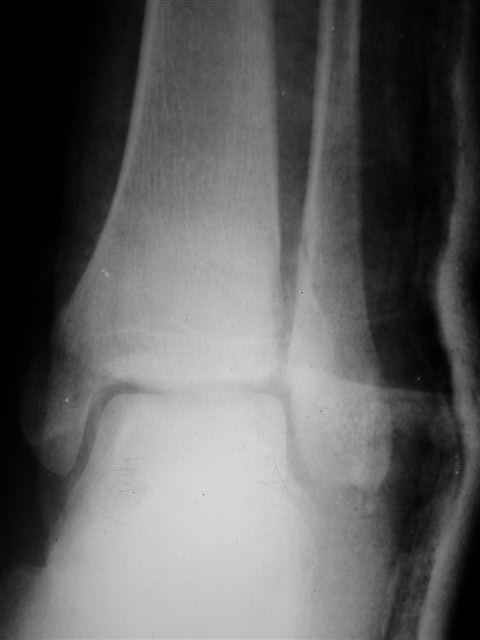

В первом письме я упомянул о закрытом повреждении правого голеностопного сустава, эверсионно-пронационный механизм травмы - перелом внутренней лодыжки( поперечный, на уровне суставной щели) и отрывной перелом бугорка Chaput. После обработки открытых переломов бедра и большеберцовой кости в эту же сессию перелом внутренней лодыжки фиксировал двумя расходящимися спицами, бугорок Chaput двумя тягловыми винтами 3,5 мм. Раны заживают благополучно. Учитывая повреждение наружной группы мышц, активное разгибание в голеностопном суставе ограничено. Пассивная + пассивно-активная мобилизация голеностопного сустава с физиотерапевтом.

Я предупреждал, что ничего сверхъестественного. Каюсь, что одна из спиц прошла несколько дальше, чем нужно было, но главное - перелом стабилизирован и больной работает суставом в полном объёме, несмотря на представленную раннее травму коленного сустава.